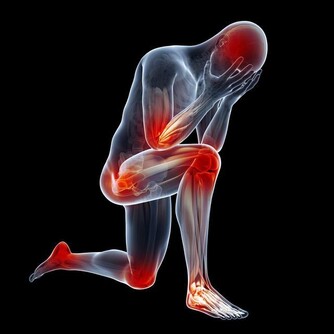

4、通常大家將胸腔以下的腹部稱為肚子,這個範圍較大。肚子疼與很多原因有關,但如果表現為臍周和下腹部疼痛,則往往是腸道病變。

5、胸部出現灼熱感或者莫名的胸痛、胸悶、氣短:胸部出現灼熱感是食道損傷的一個常見症狀,如果大家最近兩三個月頻繁出現灼熱感或者莫名的胸部疼痛,那就要要警惕食道癌或者胃癌了。

6、長期消瘦、時常覺得疲倦乏力:一些胃腸部腫瘤出現惡化的人往往還會出現類似消化不良、食慾不振等症狀,表現為消瘦,時常覺得疲倦乏力,失眠多夢等。